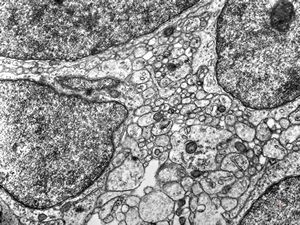

F,49y. | hemangioblastoma

M,39y. | hemangioblastoma

M,39y. | hemangioblastoma

M,21y. | hemangioblastoma

F,49y. | hemangioblastoma